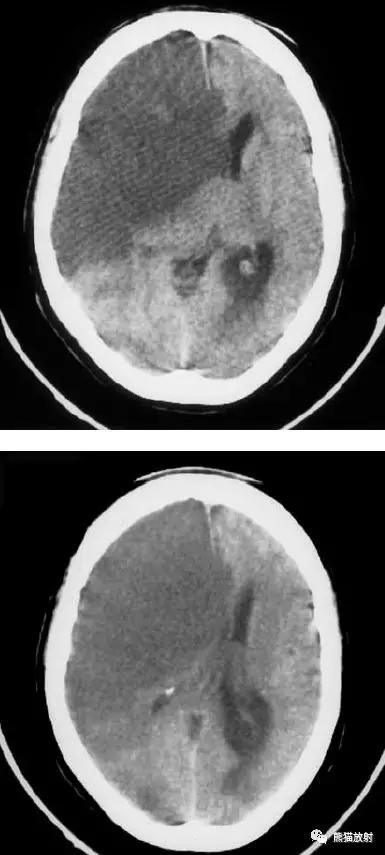

右侧大脑中动脉区域梗死的典型演变:

a)急性期

b)早期亚急性期(2天,从临床起病开始)

c)亚急性晚期(2周后)

d)慢性期(一年后)